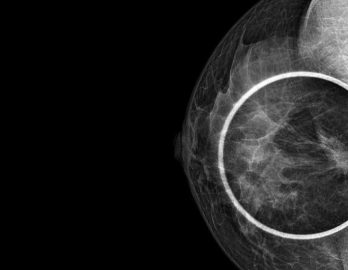

Sabemos que visitar un centro médico a veces genera nervios. Por eso, hemos creado un ambiente cálido, moderno y 100% seguro para ti. Desde nuestra cómoda sala de espera hasta nuestras áreas de ecografía, mamografía y rayos X, cada rincón está equipado con tecnología de última generación y diseñado para que te sientas en confianza.